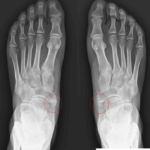

19 평발, 요족 flat foot, cavus foot

17 발 바깥쪽이 아파요 Outer foot pain

[doctormodu]1 os subfibularae

[doctormodu]1 accessory navicular bone x-ray